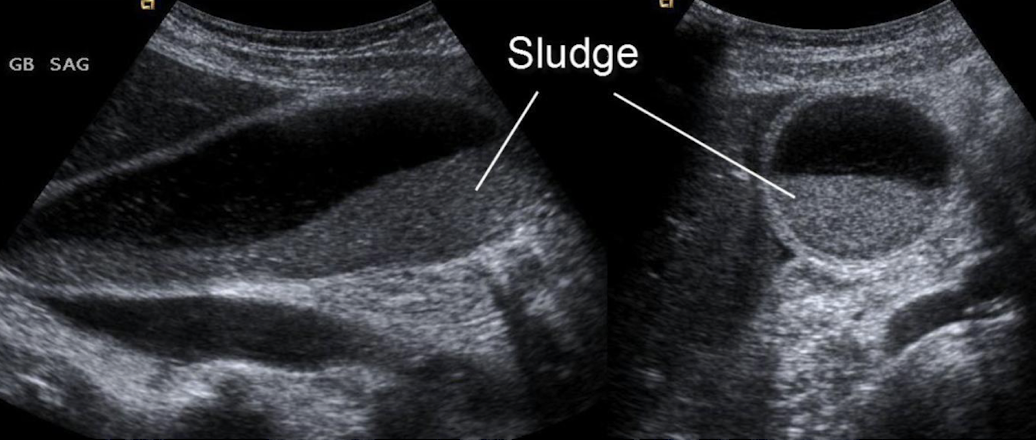

GB sludge

aka thickened bile

results from bile stasis

gravity dependent; slowly resettled upon LLD/LLO repositioning

can cause stone formation, biliary colic (abdominal pain), acalculous cholecystitis, and pancreatitis

SONO: non-shadowing, low-level internal echoes (echogenic)